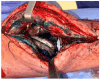

Background: as the demand for total joint arthroplasty continues to grow each year, the healthcare burden is expected to increase due to periprosthetic joint infection (PJI). This review article aims to highlight the significance of biofilms in the pathogenesis of PJI and introduce alternative therapies that prevent bacterial adhesion to implants or enhance their eradication when infection occurs.

Search strategy: we conducted a bibliographic search in PubMed using the following MeSH terms as follows: "no antibiotic treatment of PJI", "bacterial biofilm eradication agents", and "unconventional prevention of PJI", among others. Most important results: after an initial analysis of the literature, we selected the most significant topics on novel PJI treatment methods and prevention strategies. A second PubMed search highlighted the following therapeutic modalities: the application of hydrogels on implant surfaces, the use of phage therapy, lysostaphin and antimicrobial peptides, the implementation of two-stage debridement, irrigation, implant retention and antibiotic therapy (DAIR), the intra-articular antibiotic infusion, and the use of methylene blue for biofilm eradication.

Conclusions: the use of new cement spacers with xylitol, ammonium compounds, or silver nanoparticles is another promising technique to increase the eradication rate in two-stage revision. It is important for professionals to deeply understand the pathogenesis of PJI and the role of biofilms in its development in order to become familiar with these novel techniques that could reduce the burdens on healthcare systems.